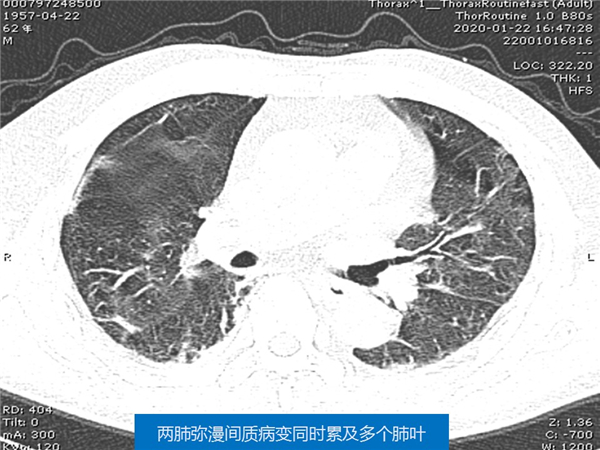

【病例分享】新型冠狀病毒感染肺部CT影像4例(常德市第一人民醫(yī)院)